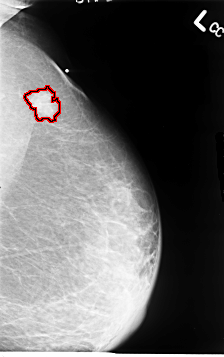

B_3064_1.LEFT_CC

LEFT_CC LINES 4656 PIXELS_PER_LINE 2944 BITS_PER_PIXEL 12 RESOLUTION 50 OVERLAY

FILE: B_3064_1.LEFT_CC.OVERLAY

TOTAL_ABNORMALITIES 1

ABNORMALITY 1

LESION_TYPE MASS SHAPE IRREGULAR MARGINS SPICULATED

ASSESSMENT 4

SUBTLETY 4

PATHOLOGY MALIGNANT

TOTAL_OUTLINES 1

BOUNDARY